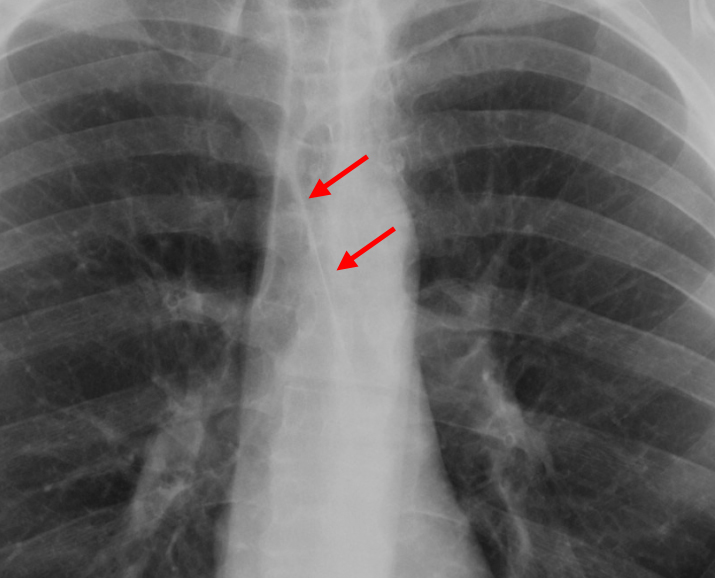

Gallery Anatomy Images Anterior junction line

Anterior junction line